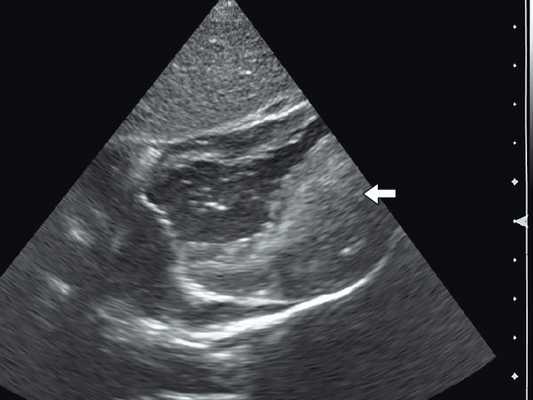

Рабдомиома сердца эхографически выглядят как достаточно четко очерченные образования. Чаще всего располагаются в миокарде левого желудочка, реже - в правом, еще реже - в предсердиях, кавоатриальных и атриовентрикулярных соединениях, эпикарде. Метастазирование не типично [8]. Наличие двух и более рабдомиом четко коррелирует с туберозным склерозом, одиночные рабдомиомы сердца такой связи, как правило, не имеют. По нашему опыту (18 пациентов), чем меньше объем новообразования, тем выше акустическая плотность, приближающаяся к эталонной эхоплотности (эндо-, эпи- и перикард). Эхоплотность больших рабдомиом практически не отличается от эхоплотности миокарда. В толще новообразования выявляются мелкие эхонегативные очажки (области некрозов) и эхопозитивные очажки (отложения кальция) (рис. 3).

Рис. 3. Эхокардиограмма гигантской рабдомиомы (стрелка) у девочки марфаноидного статуса без признаков туберозного склероза (субксифоидальный доступ).